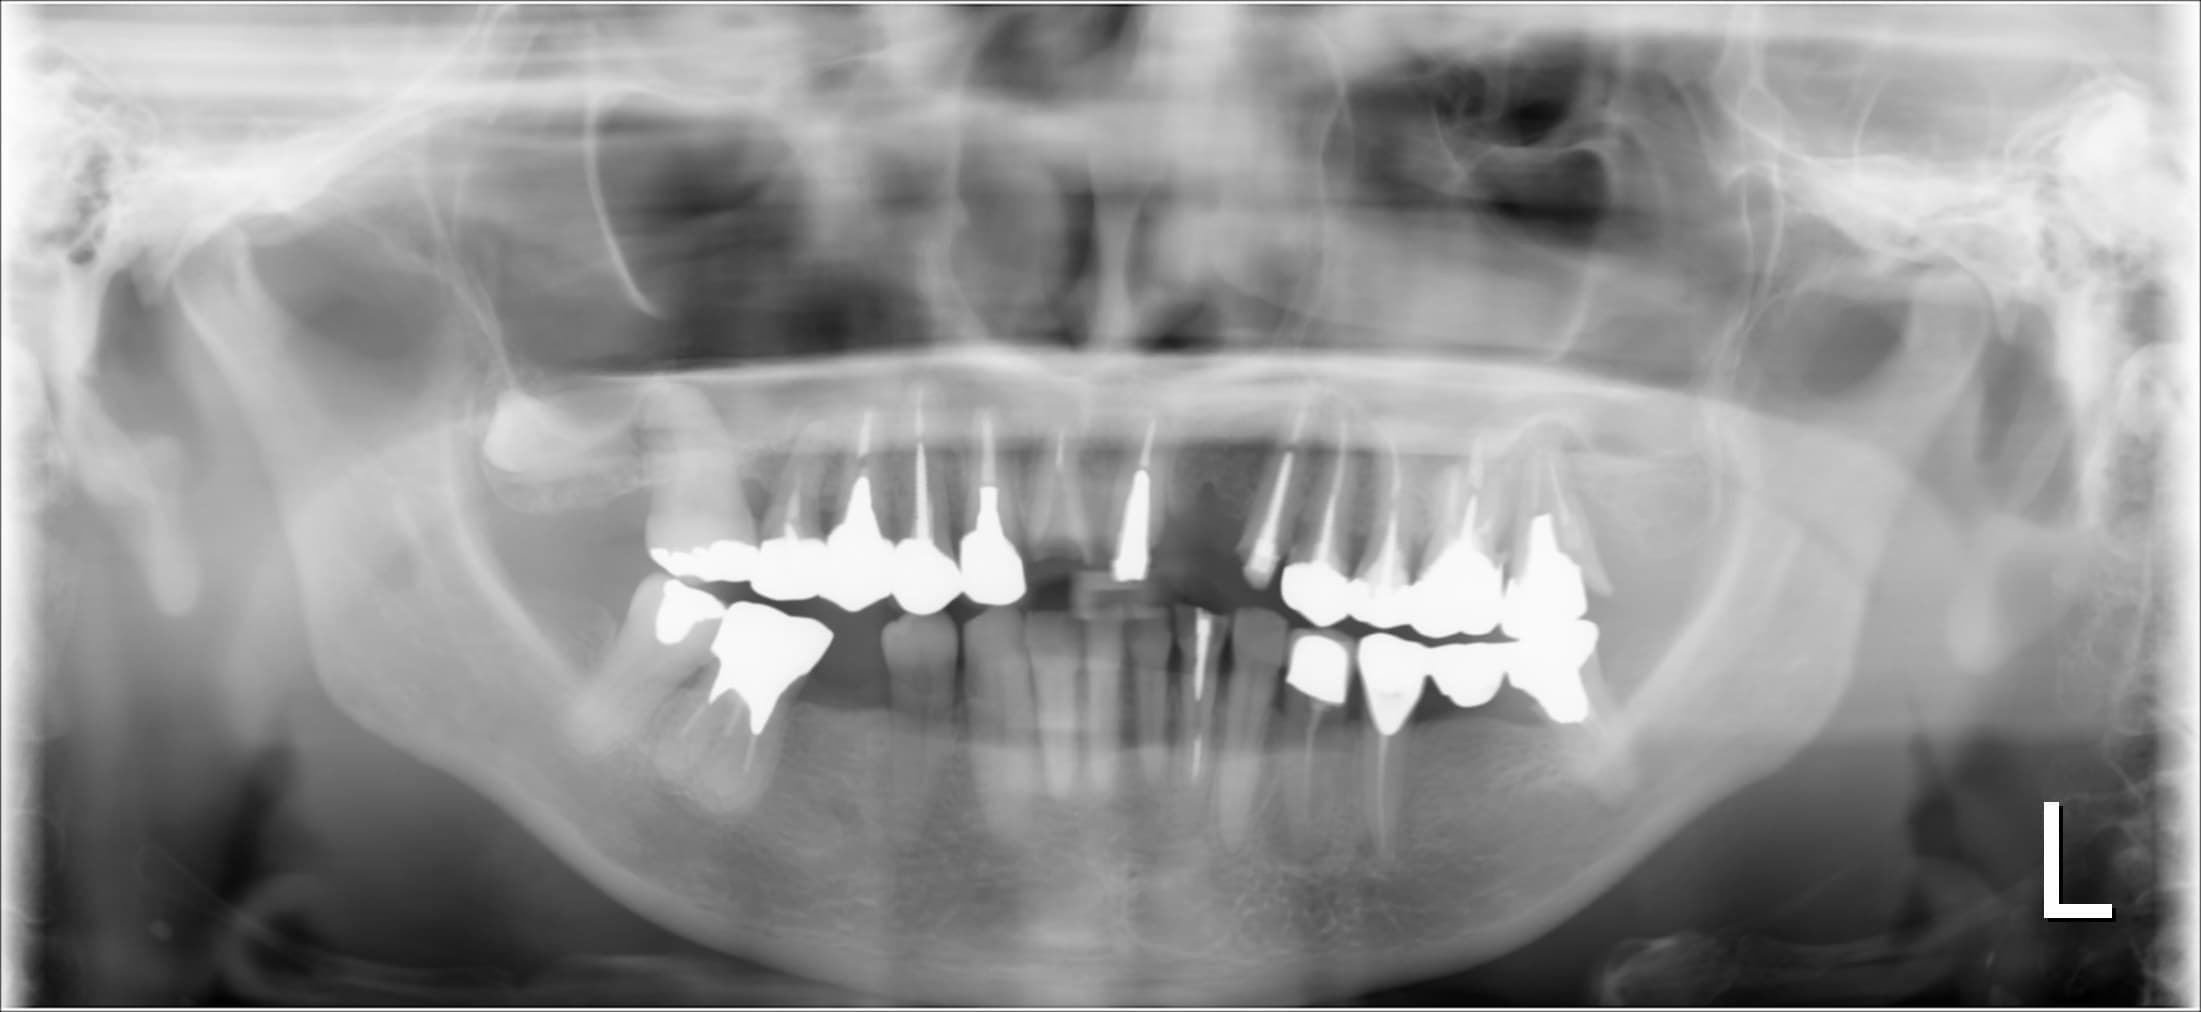

治療前

土台に使用していた歯の状態と、噛み合わにも問題があったのですが、非常に出血が多く、先ずは歯周病を改善する必要がありました。

そもそも歯という組織は、顎の骨の中に埋まって支えられており、その骨の上を歯肉に覆われています。

そして歯周病は、細菌感染により歯を支える骨が溶けてなくなる病気です。

しっかりと治したいと考えた時、歯そのものが抱える問題の解決も必要ですが、歯を支える環境を整備する事も非常に重要なことです。